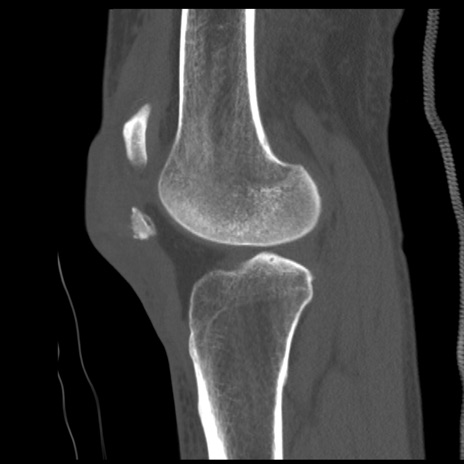

症例28 右膝関節CT(矢状断像)

右膝関節CT